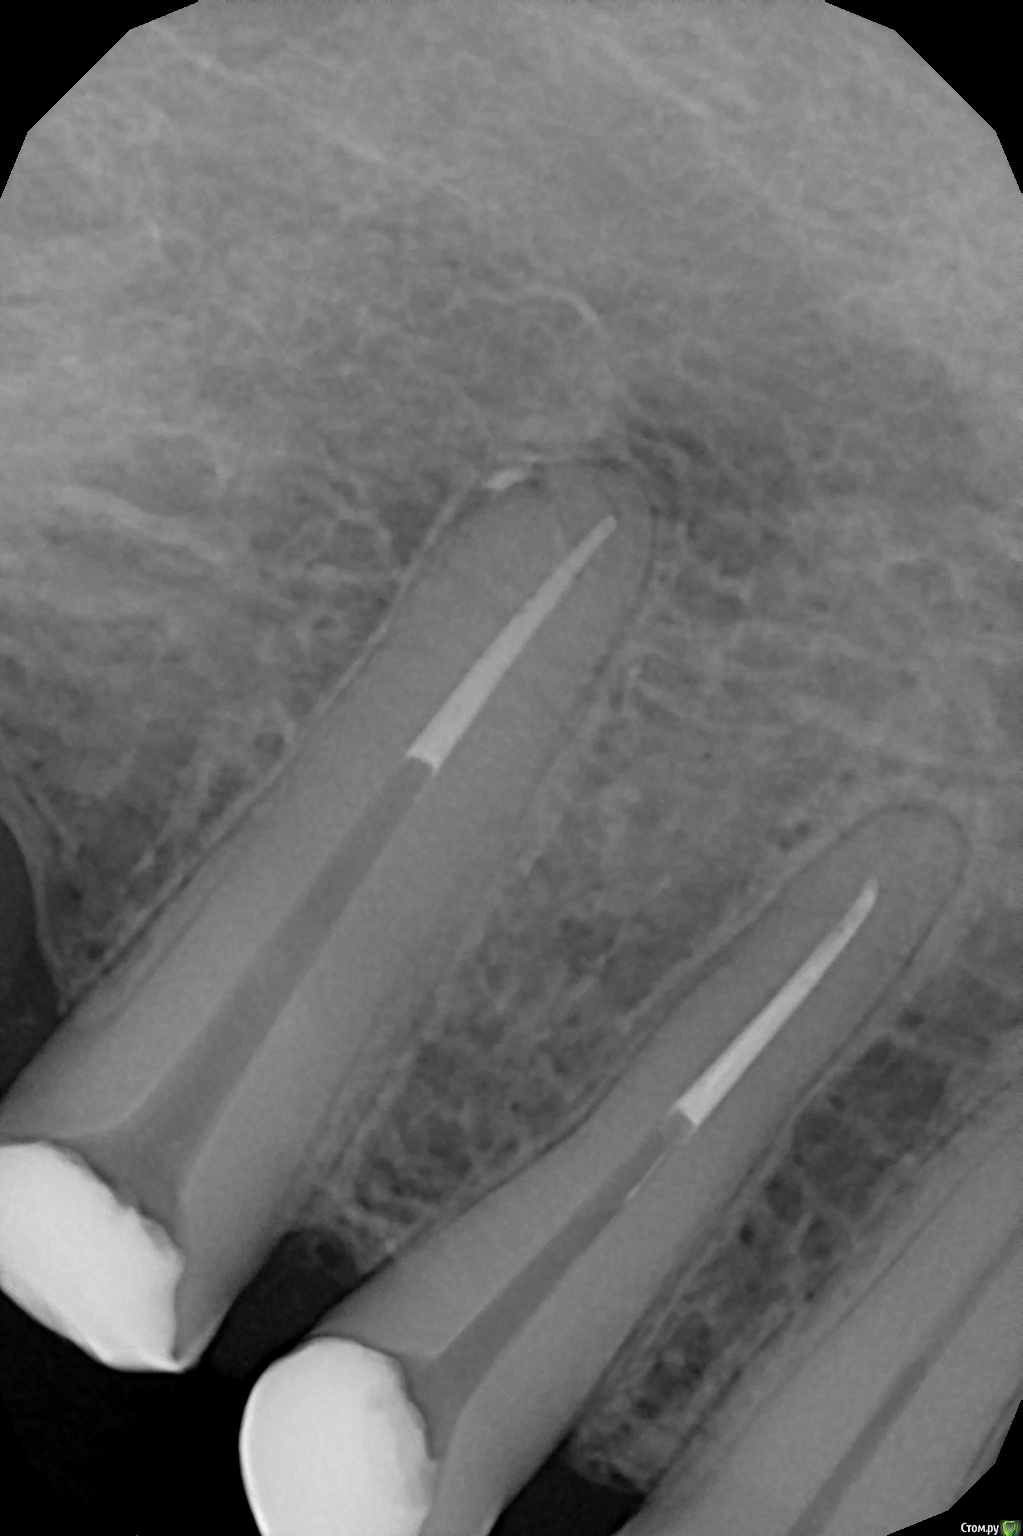

Нижние левые 4-5, было проведено эндодонтическое лечение каналов, для последующей установки культевой вкладки и установки коронки. После наложения временной пломбы прошёл почти месяц, а 5ка болезненно реагирует на постукивание по зубу. Почему так может быть и что с этим делать?

post-27969-0-75935000-1535447612_thumb.jpg